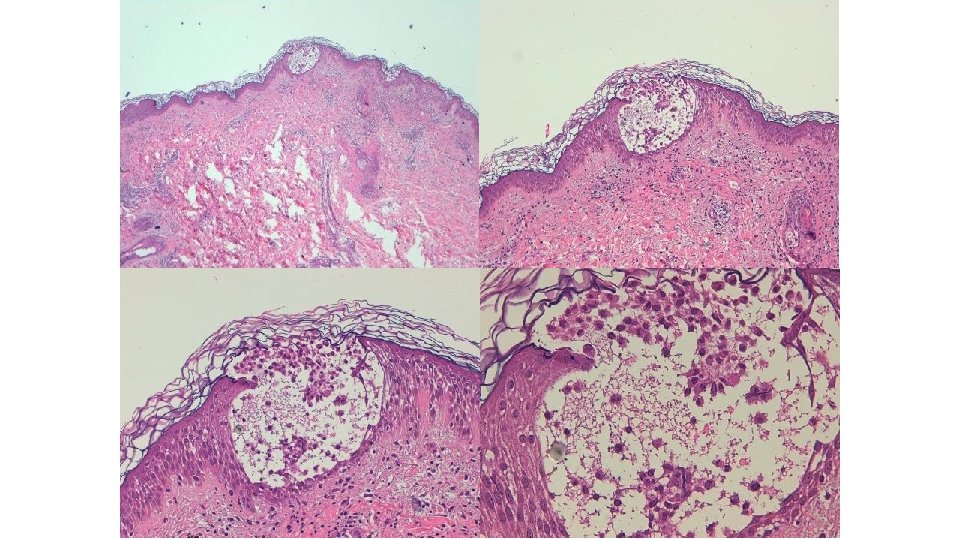

Hipeplasia epidérmica, edema y espongiosis dermis, degeneración hidrópica epidermis

Diferencias entre eritema acral de la QT convencinal y el síndrome mano pie de los inh multikinasa ERITEMA ACRAL QT CONVENCINOAL SINDROME PIE MANO INH MULTILKINASA Eritema y edema difuso, simétrico Hiperqueratosis localizadas Daño ductal ecrino por excreción Defecto en la reparación de la QT endotelial por bloqueo PDGF Citotoxicidad inducida por la QT Degeneración vacuolar de la Dermatitis de interfase epidermis escasamente celular, Hiperqueratosis y acantosis queratinocitos necróticos, SMEE